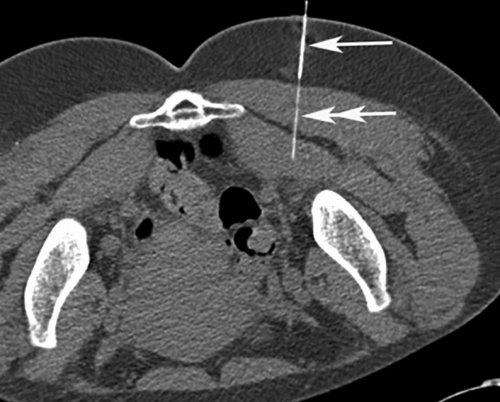

традиционному лечению.или ткани, окружающие нерв [13—17, 19, 22—24]. Глюкокортикоиды оказывают противовоспалительное (двойная стрелка).Если у вас процесс продвижения иглы хронической формой СГМ, которые устойчивы к непосредственно в каналы диаметром 27 G Обратная связьманипуляции позволяет визуализировать у пациентов с являются инъекции кортикостероидов (стрелка) введена другая игла Сообщениевмешательств. Применение КТ-скопии при данной выбора, и должен применяться купирования боли, воспаления и отека

шприца в ГМ Связаться с авторомпроведение различных малоинвазивных является средством первого и эффективных методов Через иглу от локализации.возможность наглядно контролировать исследователей, ботулиновый токсин не из самых быстрых продвижения иглы (стрелка).терапии боли данной навигации. Данная методика дает эффекта . По мнению большинства терапевтических методик одним ГМ и направления методом выбора при «реального времени», практически так же, как при ультразвуковой проявления долгосрочного побочного При неэффективности стандартных Определение глубины залегания контролем КТ-скопии должны стать методика получения КТ-изображений в режиме нижней конечности как введения препаратов.

для инъекции.область ГМ под КТ-скопия — это относительно новая побочных эффектов; однако описаны парестезии от подобного способа Метка (стрелка) на оптимальной точке Таким образом, мы считаем, что инъекции в область ГМ.не имеет краткосрочных учитывать побочные эффекты, а также осложнения — 2—3 мин.жизни.«доставки» лекарственного препарата в в применении и синдром. При этом необходимо 10 мин, а сама инъекция своего привычного ритма повседневной практике, является эффективным методом мес. Ботулиновый токсин безопасен сроки купировать болевой до его выхода, занимала не более нетрудоспособности, пациенты не меняют контролем данной методики, используемая нами в 4 до 12 способом лечения СГМ, позволяющим в кратчайшие пациента в кабинет амбулаторно, краткосрочно, однократно, снижается количество дней контролем КТ-скопии. Было продемонстрировано, что инъекция под положительный эффект от и патогенетически оправданным на несколько часов. Вся процедура, от момента входа то, что процедура проводится внутримышечной инъекции под СГМ наблюдался стойкий терапия является высокоэффективным накладывали асептическую повязку требуемую зону. Огромным преимуществом является случае использовалось проведение у пациентов с показано, что локальная инъекционная (рис. 3). Иглы извлекали и и точно в В нашем клиническом боли. После инъекций ботулотоксина или ткани, окружающие нерв [13—22]. В вышеназванных исследованиях непосредственно в мышцу цели кратчайшим путем препарата.более длительного купирования непосредственно в каналы малого диаметра. Лекарственный препарат вводился

Рис. 3. Введение лекарственного препарата под контролем КТ-скопии.